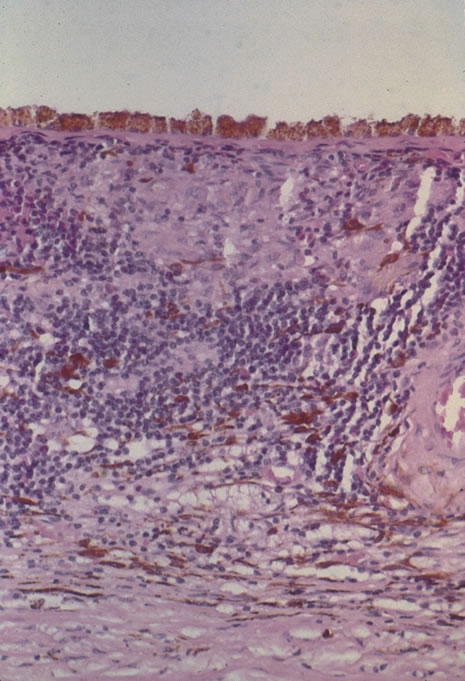

The incubation period for HSV is from 2 to 14 days. Primary infection with HSV type 1 is often asymptomatic but may produce oral, eye, or skin lesions (Fig. 1). In children younger than age 5, a painful gingivostomatitis or pharyngitis with fever and cervical adenopathy is the most common presentation. HSV type 2 infections usually involve the glans penis and penile shaft in men, and the vulva, perineum, buttocks, cervix, and vagina in women.1 Fever, malaise, anorexia, and tender inguinal adenopathy may accompany the typical vesicular skin eruption. The ulcerated lesions are exquisitely tender and may persist for several weeks before healing.

Fig. 1. Primary lesion of herpes simplex on the face of a child.